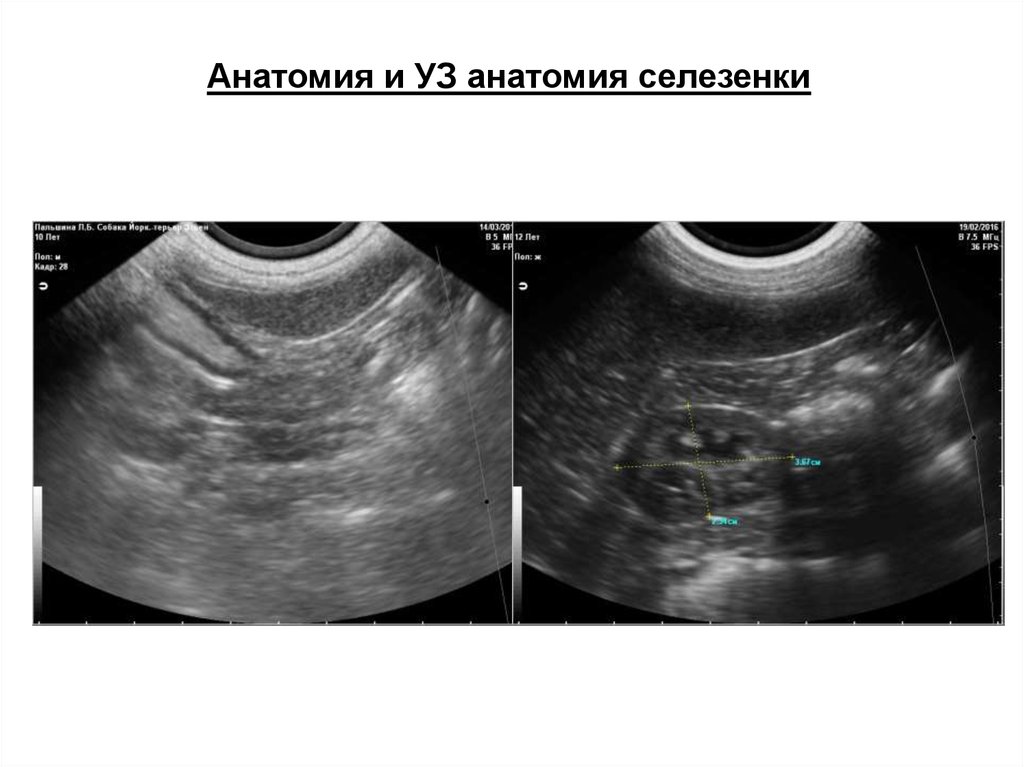

Анатомия и УЗ анатомия селезенки